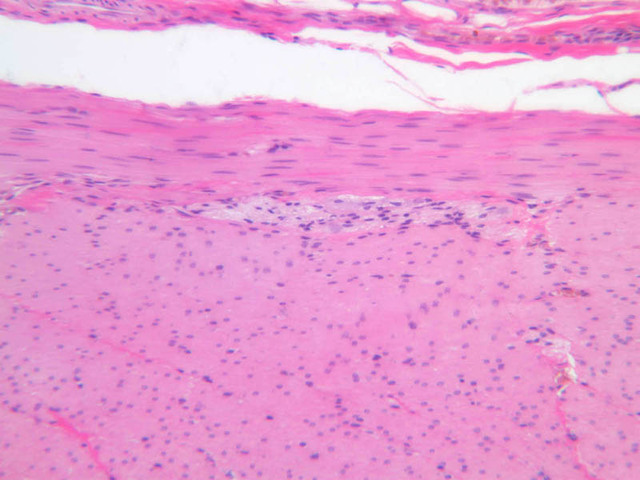

Using the low or medium power objective, scan the section of the rectoanal junction on slide B-26 (H&E [2.5x-labeled, 10x-labeled] [2.5x, 20x, 40x] [2.5x, 20x-labeled, 40x] [20x, 40x] [20x, 40x] [20x] [2.5x, 10x, 20x, 40x]) . Proximally, the rectal mucosa exhibits crypts of Lieberk\xFChn and the simple columnar epithelium is exceptionally rich in goblet cells. As you trace the epithelium towards the anus, you will find that the crypts disappear, then the simple columnar epithelium gives way to stratified squamous epithelium, often with a narrow intervening swath of stratified cuboidal or stratified columnar epithelium. Just proximal to the anal orifice keratin appears and just distal to the anal orifice you may be able to find sweat glands, sebaceous glands and hair follicles.

B26, Anal Canal, 2.5x Labeled (H&E) B26, Anal Canal, 10x Labeled (H&E) B26, Anal Canal, 2.5x Labeled (H&E) B26, Anal Canal, 20x Labeled (H&E) B26, Anal Canal, 40x Labeled (H&E) B26, Anal Canal, 2.5x Labeled (H&E) B26, Anal Canal, 20x Labeled (H&E) B26, Anal Canal, 40x Labeled (H&E) B26, Anal Canal, 20x Labeled (H&E) B26, Anal Canal, 40x Labeled (H&E) B26, Anal Canal, 20x Labeled (H&E) B26, Anal Canal, 40x Labeled (H&E) B26, Anal Canal, 20x Labeled (H&E) B26, Anal Canal, 2.5x (H&E) B26, Anal Canal, 10x (H&E) B26, Anal Canal, 20x (H&E) B26, Anal Canal, 40x (H&E)